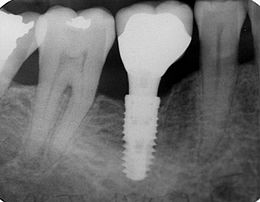

L'objectif de ce cours est d'acquérir la pratique nécessaire au positionnement d'implants. Les étapes à suivre sont:

Effectuer les différentes techniques pour la pose d'un implant.

Chaque étudiant placera au moins 20 implants (incluses dans le prix du cours). Il est possible d'intensifier la pratique avec un coût supplémentaire.

Le cours dure 5 jours à Maringa au Brésil (implant posé neodent (straumann)) ou à Sao Paulo si le groupe dépasse 4 praticien.